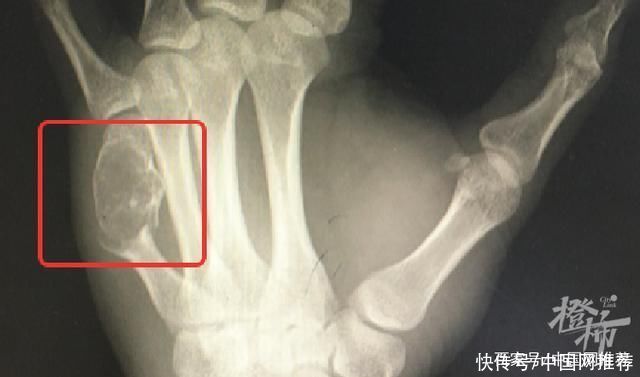

“这可不是一般的键盘手,你左手这根骨头里的东西,其实是内生性软骨瘤,它把你正常的骨头都‘融’成‘豆腐渣’了。”医生解释,内生性软骨瘤是一种发生于骨内的良性骨肿瘤。一般没有症状或伴有轻微酸痛、无痛性肿胀,看起来更像肢体的局部肿胀,并且其生长速度缓慢,数年内体积也无明显变化,所以多数病人是出现了病理性骨折后才被检查出此病。目前经手术,黄先生的左手恢复情况良好。